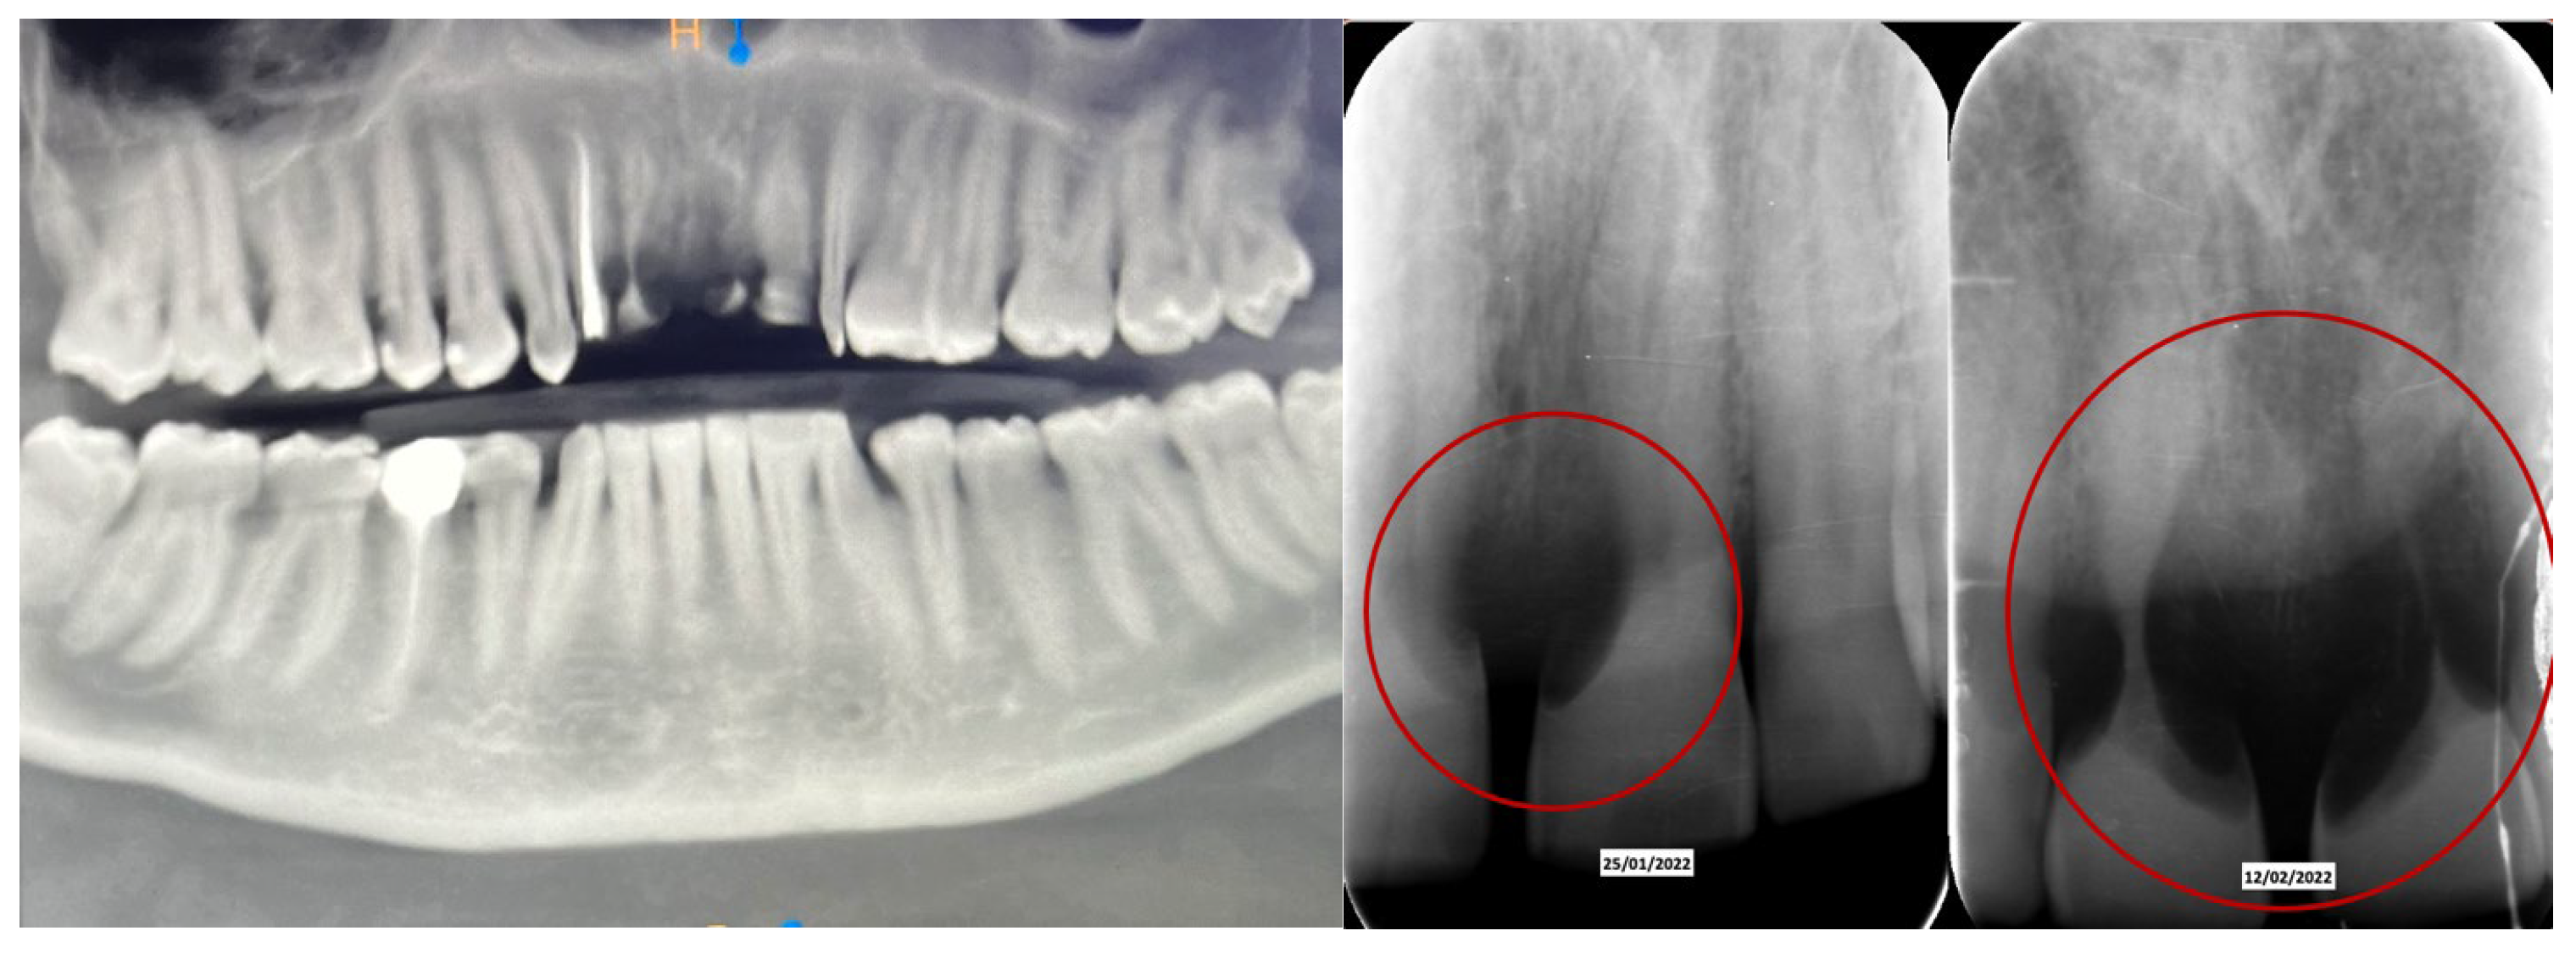

A 52-year-old patient, affected by non-Hodgkin lymphoma since March 2020 and treated with denosumab until June 2021, in clinical remission, presented in January 2022 for observation with multiple root resorptions, not of endodontic origin; it initially affected 22-21-11, but then, with rapid evolution, also affected 23-12-13-14-15-16-17-46-47, without referred pain. The resorption phenomena ended in September 2022. Since then, every radiographic check-up carried out to verify the progress of the regenerative bone surgeries has confirmed the arrest of the progression of the resorption phenomenon affecting the residual dental roots. In February 2022, as soon as responsibility for the patient’s care was assumed, in agreement with the oncology department of the hospital in Bergamo in which he was in care, given the severity of the lesions present (Figure 2), it was decided to extract the teeth (22-21-11), with a surgical toilet of the alveolus associated with decontamination with dye-free laser photodynamic therapy (February 2022).

Figure 2. Evolution of the external resorptions, with a rapid deterioration in only 2 weeks.

Just two weeks later, a rapid worsening was observed (documented with periapical intraoral X-rays) of the elements (13-12-23), which led to their necessary extraction (May 2022), with decontamination of the alveoli, with the beginning of a reabsorption process involving 14-15-16-46-47 (March 2022) with delivery of a removable partial prosthesis (Figure 5).

60 days after the extraction of the upper front teeth, it was discovered that the upper right premolars were also affected by significant root resorption, as well as 46 and 47 (Figure 6).